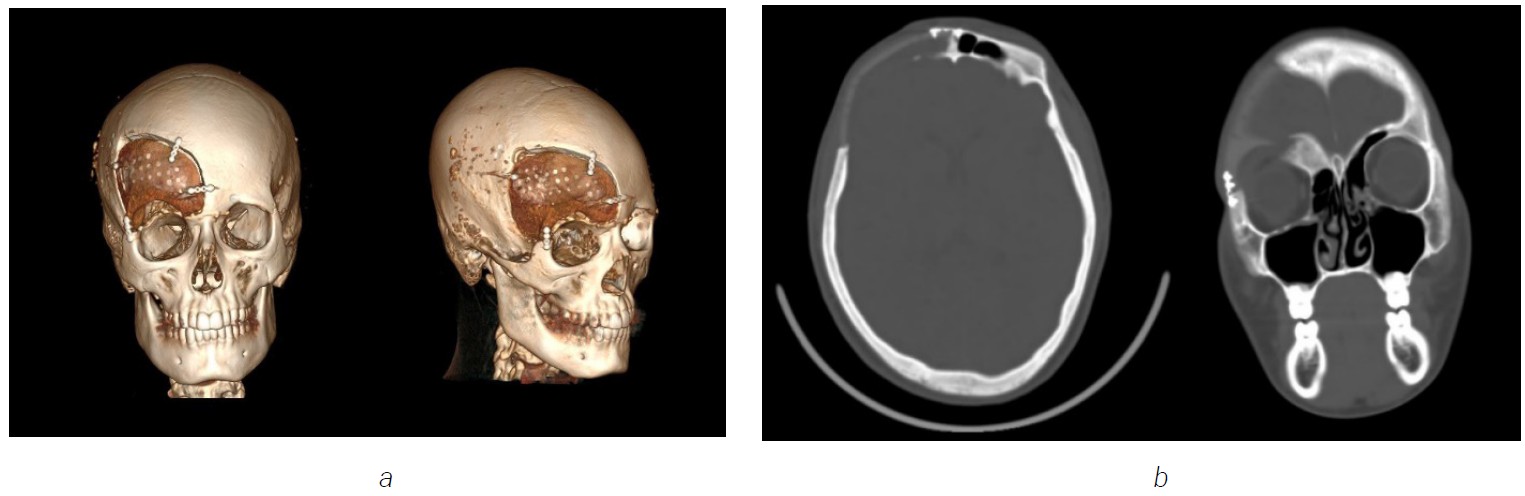

Treatment

The reconstruction of the orbital roof and frontal bone was planned and conducted by using a customized modeled implant based on polyetheretherketone (PEEK). Fibrous dysplasia of parietal bone was removed and the defect was closed using a custom made hydroxyapatite prosthesis (Figure 3).

Observation

Following an improvement in the patient’s condition after 2 weeks post-operative follow-up, the child was discharged under the care of specialists at their place of residence. During the 3 years of follow up observation, MSCT scan control did not reveal any data of progression of the disease. Additionally a successful osteogenesis was noted between the PEEK implant and the bone (Figure 4).

Fig. 3. MSCT (3D cut) scan showing post-operative surgery in 2022, with implant fixed by mini plates and mini screws on the left frontal bone and hydroxide appetite prosthesis in the left partial bone

A synthesis polyethertherketone (PEEK) implant was fixed by mini plate and mini screw to the affect area (Figure 6).

In the postoperative period, the patient received antibacterial therapy with combination of infusion pain killer and dexamethasone. The patient was discharged home in a stable condition after 2 weeks from operations.

Fig. 7. MSCT postoperative on July 2024. (a) MSCT with three-dimensional reconstruction checkup (b) postoperative coronal and axial computed tomographic image with 3D, showing no recurrence signs of the disease